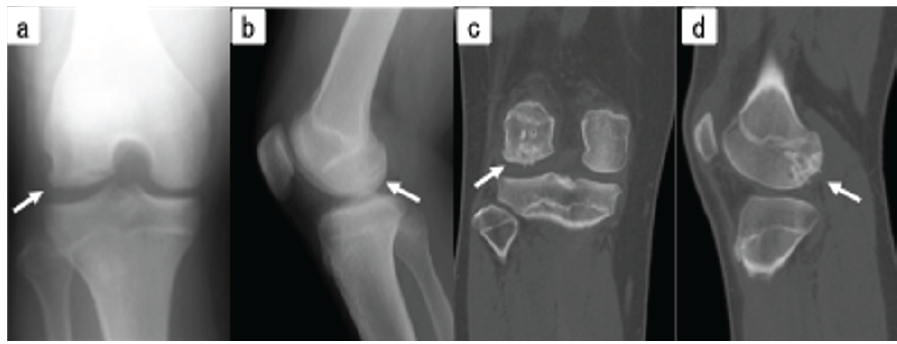

The patient was immobilized in extension for 2 weeks postoperatively and was non-weight-bearing for 6 weeks. Five months postoperatively, X-rays and computed tomography scans confirmed bony fusion (Fig. 5), and the Lysholm score improved from 29 preoperatively to 95 postoperatively. The patient returned to sports 6 months after surgery, with no symptom recurrence after 1 year.

Figure 5: (a) Simple X-ray (frontal view). (b) Simple X-ray (lateral view). (c) Simple computed tomography (coronal section). (d) Simple computed tomography (sagittal section), all showing bone fusion 5 months after surgery (white arrow).